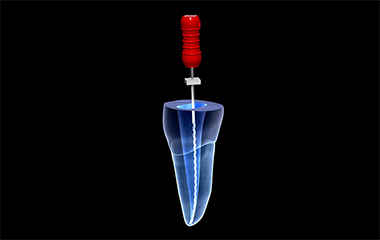

STEP02抜髄・感染根管処置

歯の中の歯髄を取り除きます。これを抜髄と言います。既に根の治療がされている歯が再感染を起こし、炎症がある場合や、歯髄が既に死んでしまっている状態の場合は感染根管処置と言い、中に入っている感染が疑われる物質を取り除きます。

STEP03根管洗浄・貼薬

根の中を洗浄・消毒し、お薬を入れます。このステップを何度か繰り返すことで、根の中がきれいになっていきます。

もともとの虫歯の大きさや、炎症の度合いによっては、この治療の回数が増えてしまうこともあります。歯の周囲の炎症がなくなるまで続けます。 -

STEP04根管充填

根の中がきれいになり、炎症(痛みや違和感)がなくなったら、最終的な防腐剤を詰めます。詰めた後は、しっかりお薬が入ったかどうかを確認するために、レントゲン写真を撮影します。

お薬を空洞なく緊密に詰めることで、細菌の再繁殖を防ぎ、長く歯を健康に保ちやすくなります。 -